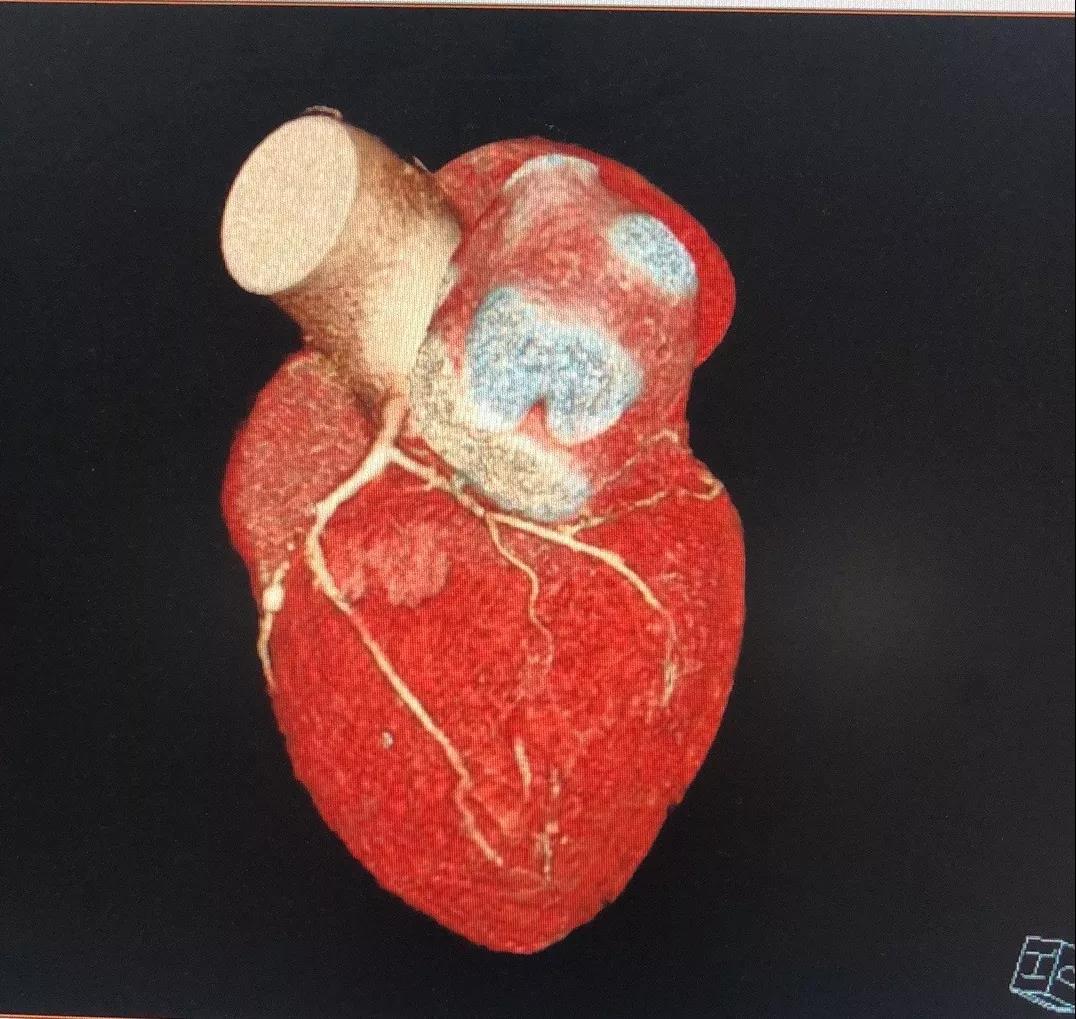

关于LCX

LCX CTA特点:

1、LCX血管相对比较“健康”;

2、LCX近中段发出比较粗大的侧枝逆向供应右冠左室后支,侧枝血管仅轻度扭曲;

3、LM前分叉相对“健康”。

有了上述信息,结合冠脉造影资料,逆向开通RCA就有了一根条件相对比较好的侧枝血管。

关于RCA

RCA CTA特点

1、入口清楚;

2、闭塞段长度小于20cm;

3、闭塞段血管无明显扭曲;

4、闭塞段内有两处明显的钙化斑块;

5、闭塞出口处血管相对比较“健康”;

6、侧枝血管汇入左室后支;

7、后三叉处的血管相对比较“健康”。